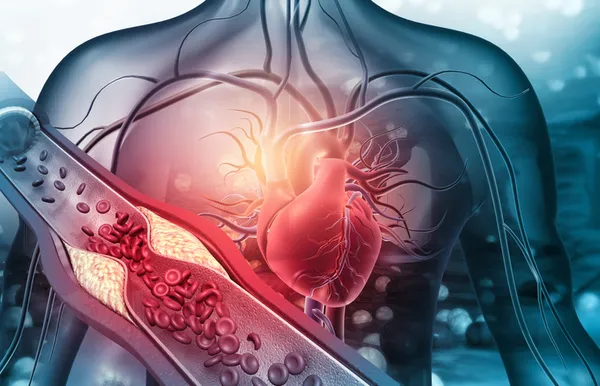

Hareketsiz yaşam tarzı ve yanlış yiyecek seçimleri yüksek kolesterole ve çeşitli kronik hastalıklara neden olabilir. Bazı gıdalar kötü kolesterolü düşürmeye yardımcı olabilir ve bunları günlük beslenmeye dahil etmek önemlidir.

Diyetisyen Garima Goyal, “Kolesterol dünya çapında önemli bir sağlık sorunudur ve yetişkinlerin tahminen %50’si yüksek kolesterol seviyelerinden muzdariptir. Yüksek kolesterol seviyeleri, önde gelen ölüm nedenlerinden biri olan kalp hastalığı riskini artırır” diyor.